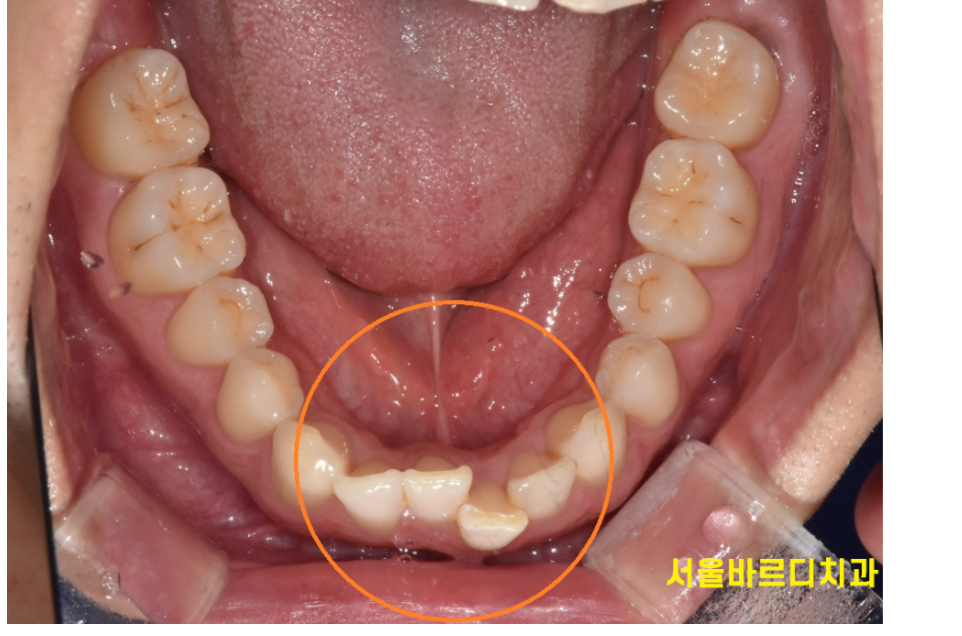

230208 삐뚤빼뚤한 앞니

삐뚤빼뚤한 치아